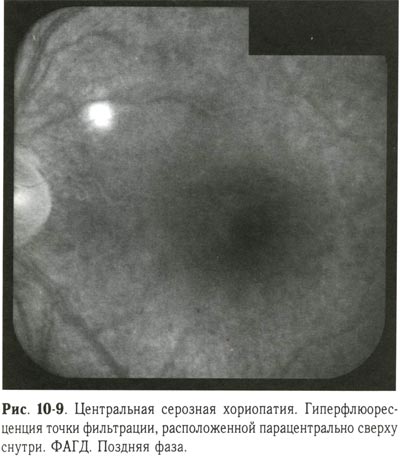

Перед лазерной коагуляцией необходимо провести ФАГД для выявления точки фильтрации и определения её локализации. Применяют 2 вида лазерной коагуляции: при наличии точки фильтрации коагуляты II степени наносятся в месте её локализации под контролем ФАГД, при отсутствии точки фильтрации производится подковообразная лазерная коагуляция по краю отслойки пигментного эпителия (рис. 10-9, 10-10; см. рис. 10-12).

Центральная серозная хориопатия. Гиперфлюоресценция точки фильтрации, расположенной парацентрально сверху снутри. ФАГД. Поздняя фаза. |